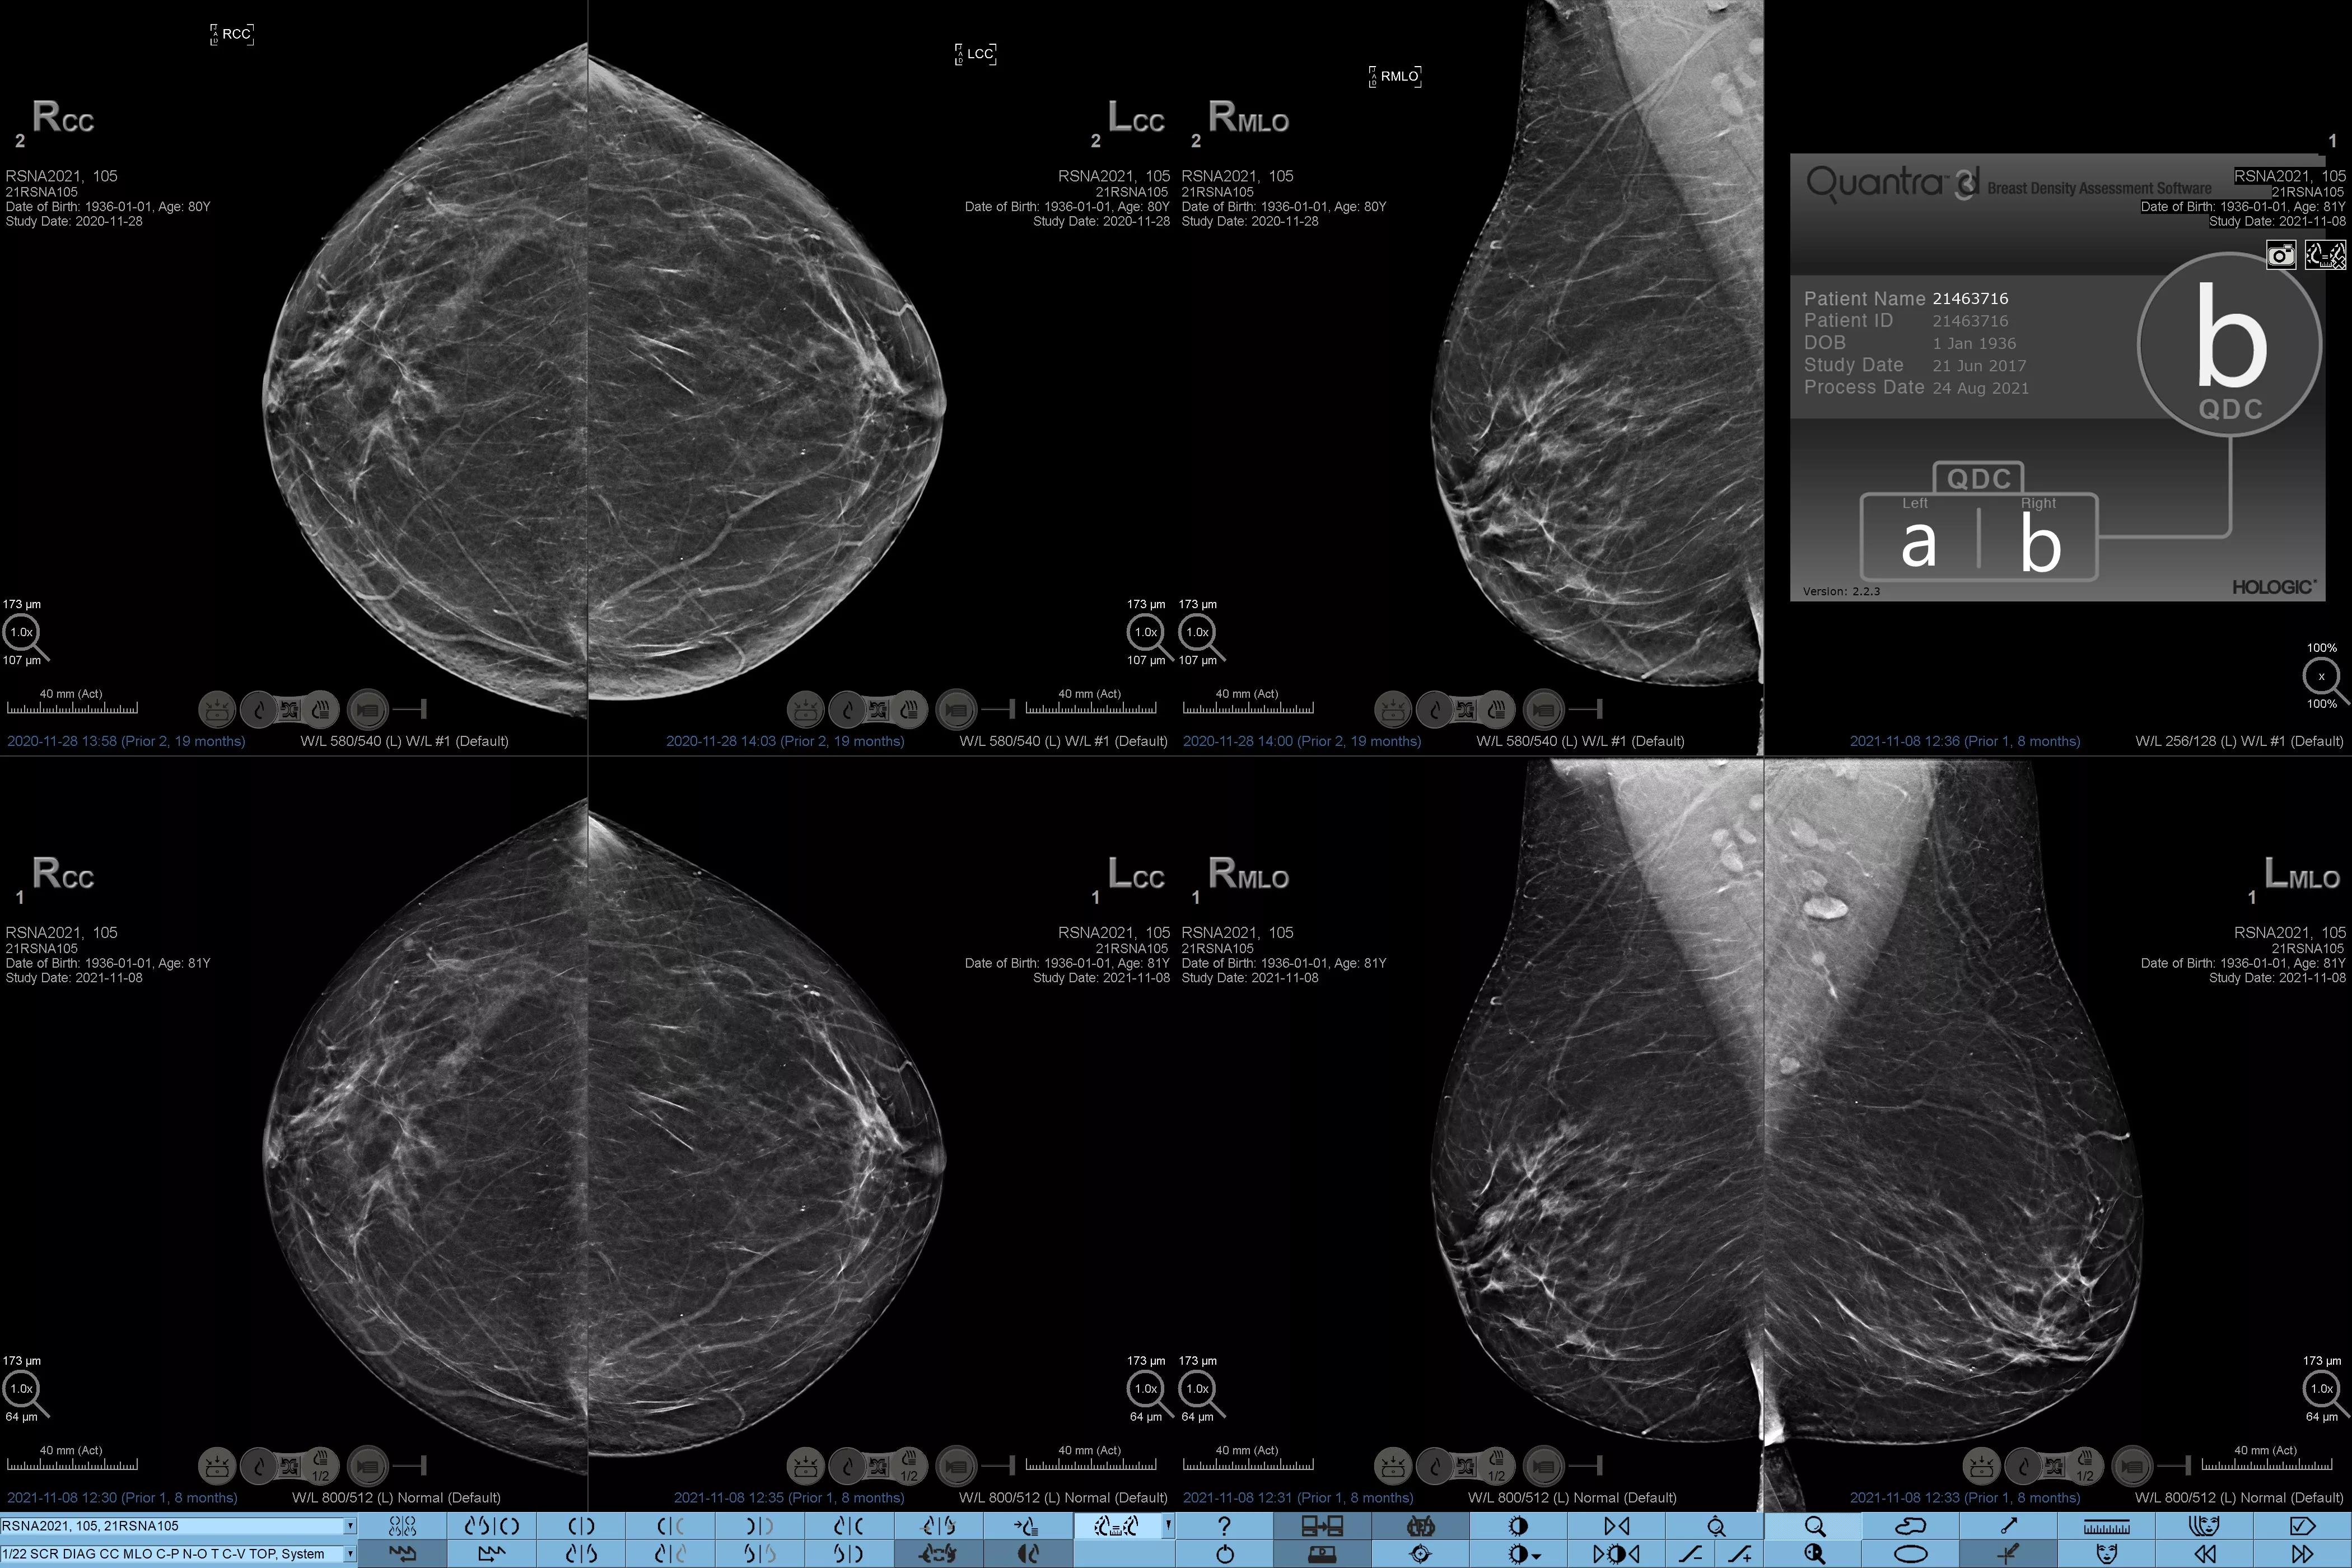

On sait qu’une densité mammaire plus élevée augmente le risque de cancer du sein chez la femme.1 Une analyse précise et objective s’avère donc primordiale. Optimisé par l’apprentissage automatique, le logiciel de la technologie Quantra analyse les images 2D™ et de tomosynthèse pour déterminer la distribution et la texture du tissu parenchymateux. Il classe les seins selon quatre catégories de composition, conformément aux recommandations de l’American College of Radiology (ACR) BI-RADS Atlas 5th Edition.2

Images de mammographies